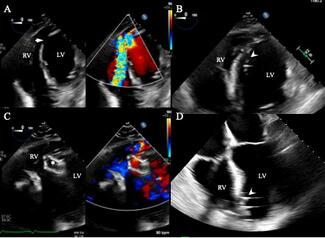

The authors present a 73-year-old female with history of rheumatic heart disease status post-mechanical mitral valve on warfarin, valvular atrial fibrillation, and alpha thalassemia who was admitted to an outside hospital with anterior...